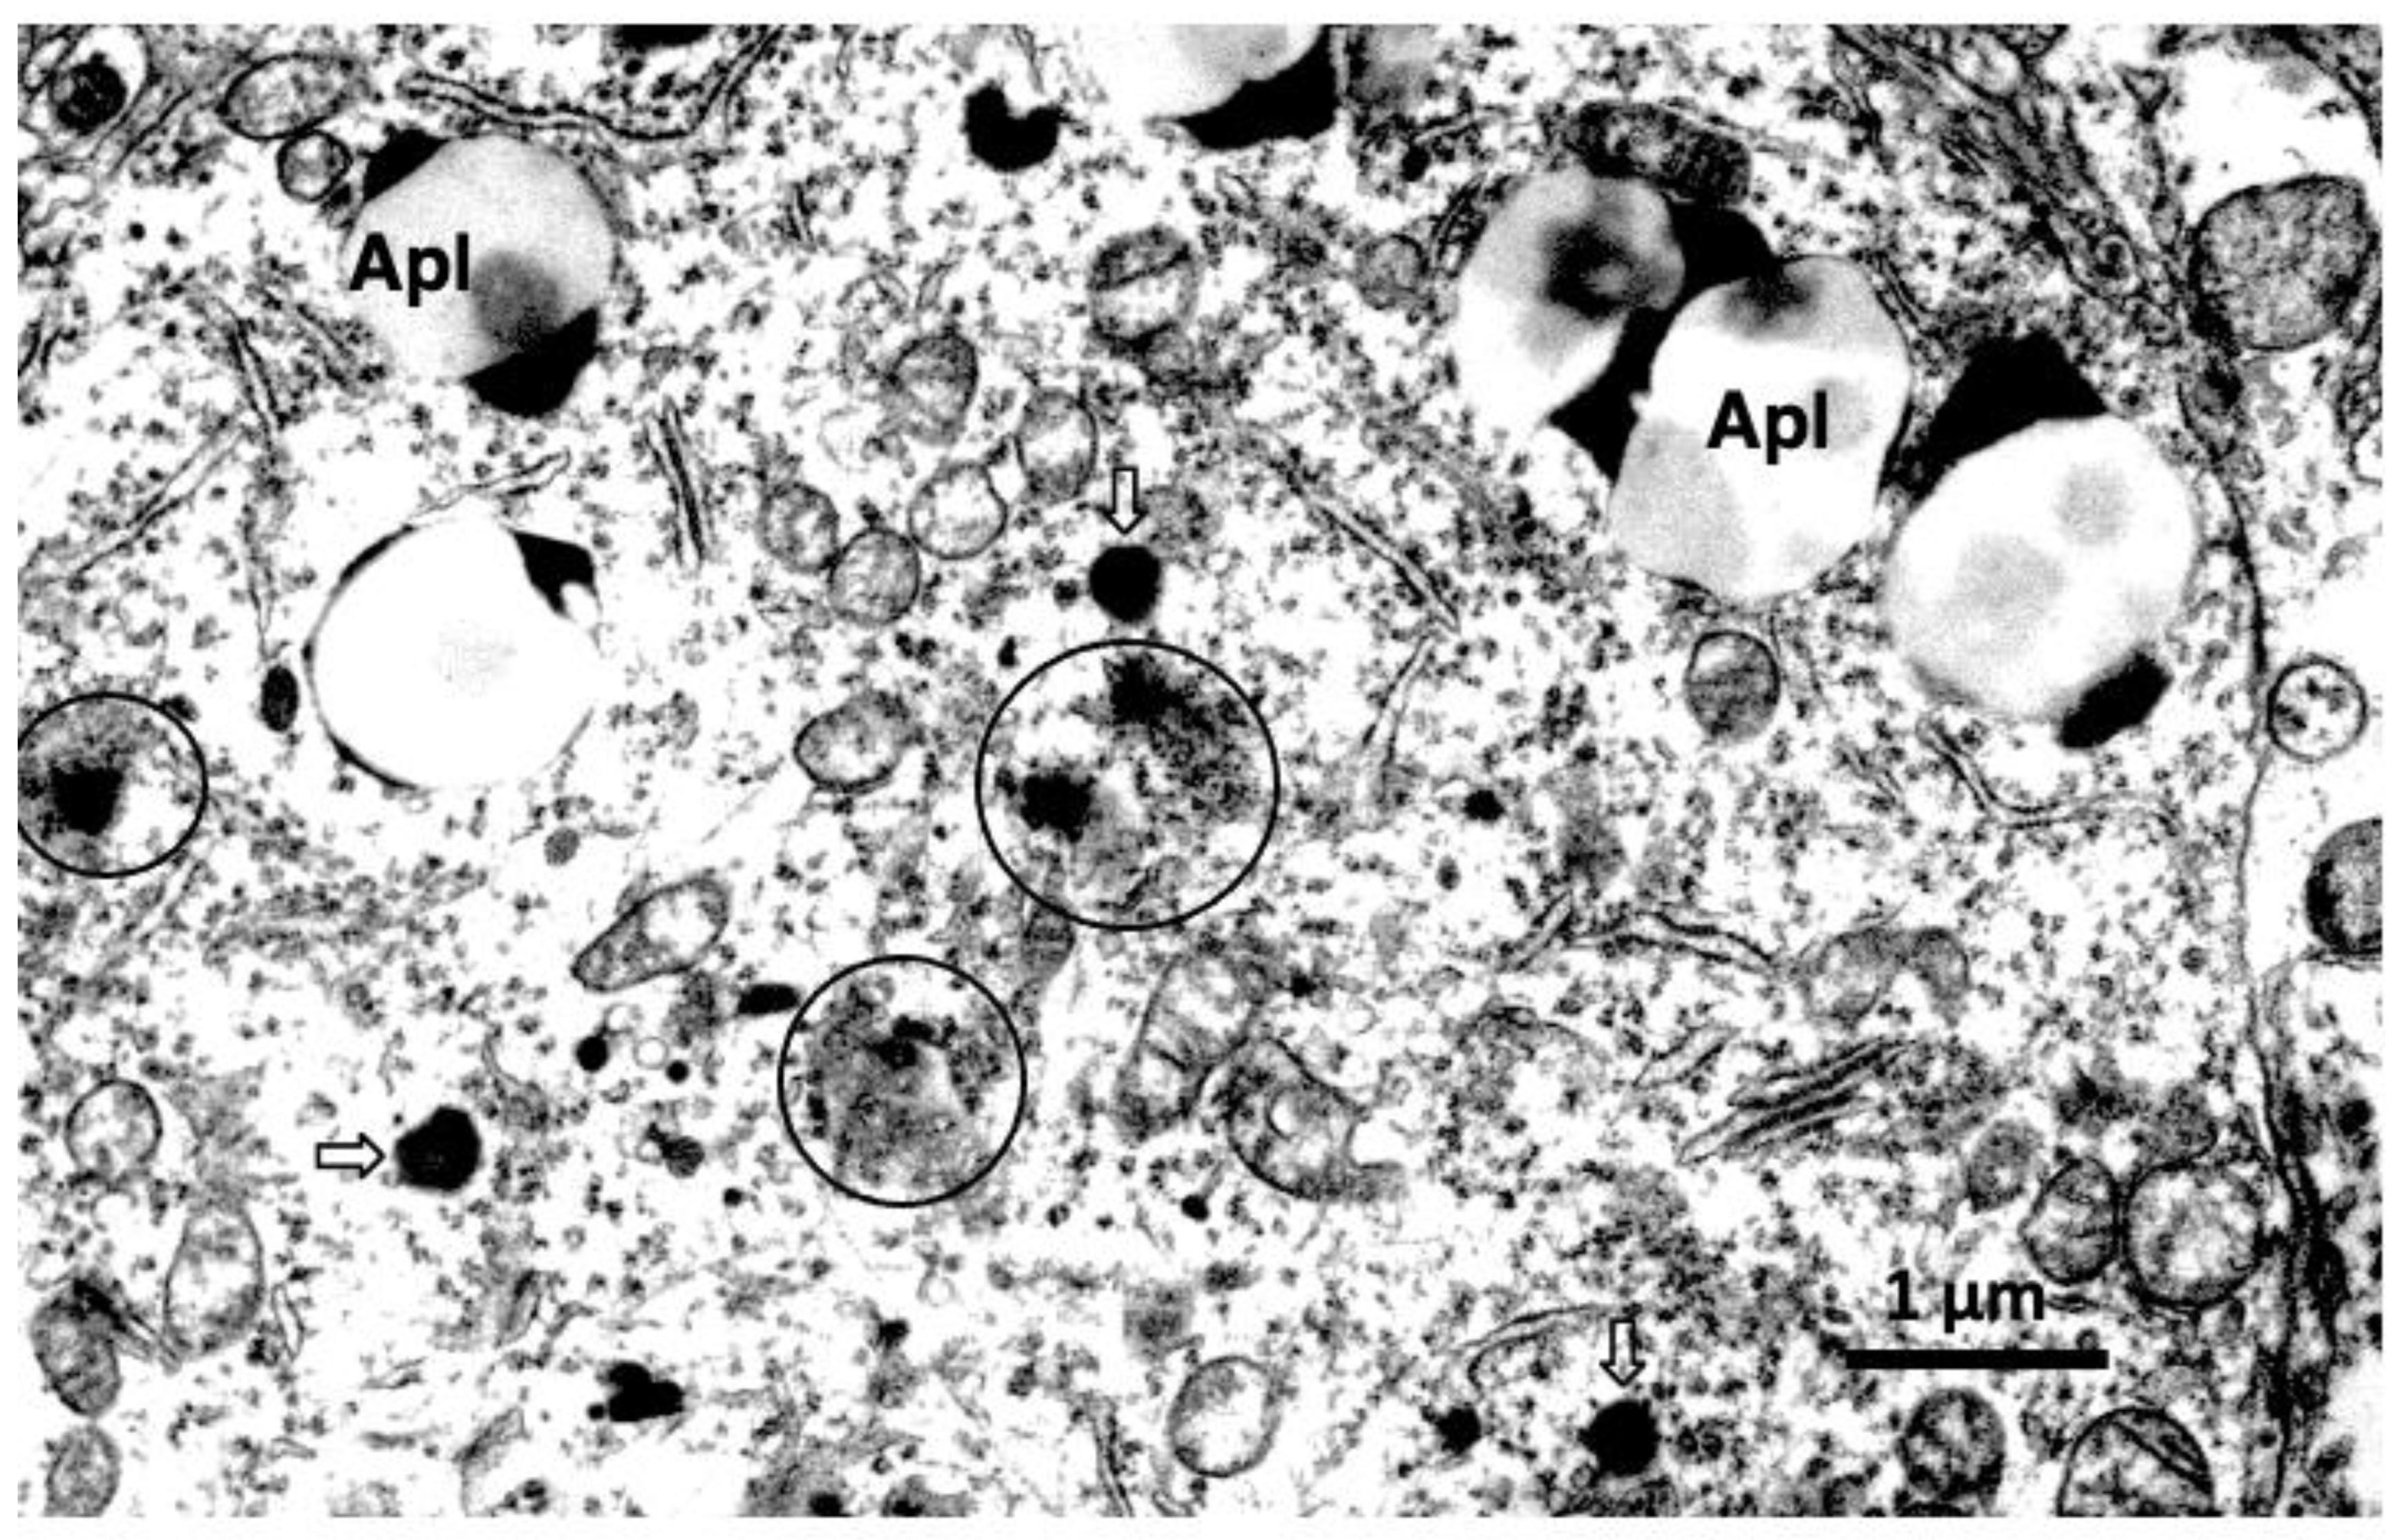

- Yamashima, T.; Mathivanan, A.; Dazortsava, M.Y.; Sakai, S.; Kurimoto, S.; Zhu, H.; Funaki, N.; Liang, H.; Hullin-Matsuda, F.; Kobayashi, T.; et al. Calpain-mediated Hsp70.1 cleavage in monkey CA1 after ischemia induces similar ‘lysosomal vesiculosis’ to Alzheimer neurons. J. Alzheimers Dis. Parkinsonism. 2014, 4, 1000139. [Google Scholar] [CrossRef]